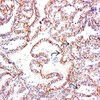

Quel est le grade ISUP/OMS de cette tumeur (image à 40x)?

Grade 1